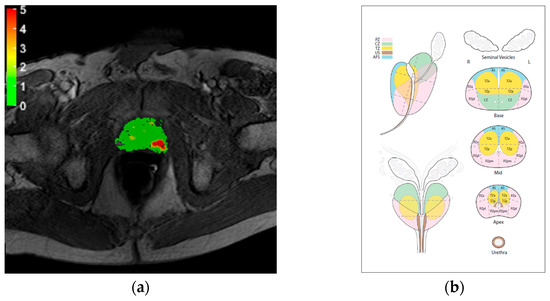

| Score | Assessment Category | MRDI Map Features |

|---|---|---|

| 0 | None (benign) | Continuous area with values below 1 |

| 1 | Very low (clinically significant cancer is highly unlikely to be present) | Continuous area with values between 1 and 2. Non-continuous area with values mostly below 2 |

| 2 | Low (clinically significant cancer is unlikely to be present) | Continuous area with values between 2 and 3. Non-continuous area with values mostly below 3 |

| 3 | Intermediate (the presence of clinically significant cancer is equivocal) | Non-continuous area with values between 2 and 4 |

| 4 | High (clinically significant cancer is likely to be present) | Continuous area with values between 3 and 4. Non-continuous area with values mostly above 4 |

| 5 | Very high (clinically significant cancer is highly likely to be present) | Continuous area with values above 4 |